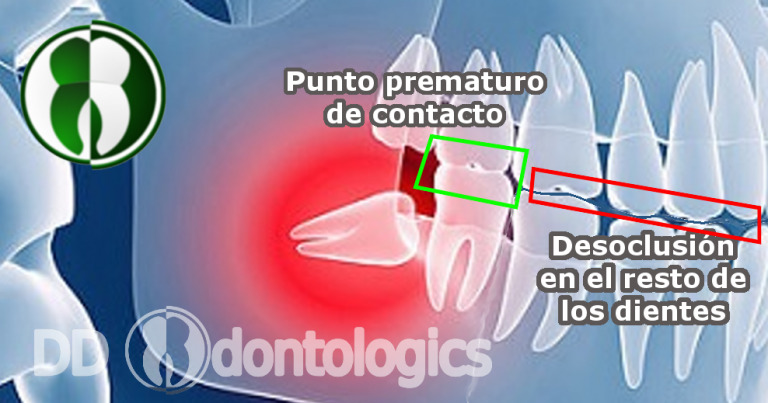

Lo que se produce cuando una muela del juicio erupciona mal o se impacta con la muela de enfrente, es que van a originar un punto de contacto prematuro con los dientes antagonistas. Lo que esto quiere decir es que, el tercer molar va a ser el primero que intervenga cuando mordemos, provocando que todos los demás dientes busquen tener contacto al mismo tiempo que la muela que acaba de salir, es por esto que los dientes pueden torcerse, inclusive hasta erupcionar un poco más, para lograr chocar todos al mismo tiempo y tener un equilibrio durante la masticación.

Algo que hay que tener en cuenta es que, una vez que los dientes se reacomodan para ceder un poco de lugar al recién llegado, no van a volver a su posición original por si solos cuando se extraigan las muelas del juicio. Haciendo necesario, el uso de brackets por cuestiones estéticas, sin importar si ya se habían utilizado antes.